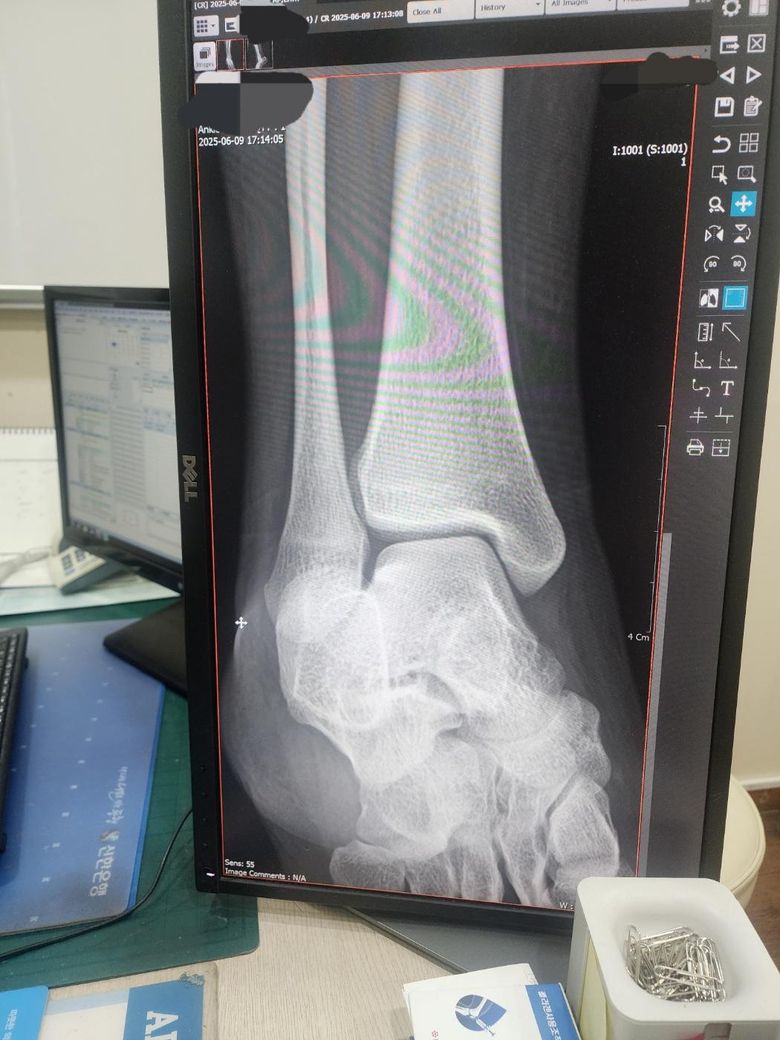

6월, 정형외과 의원에서 엑스레이 촬영 결과 '뼈가 비틀려 있다'는 소견과 함께 우측 족관절 인대 손상 진단을 받았고, 대학 졸업 후 수술 고려 가능성이 있다는 말을 들었습니다.

같은 해 9월, 대학병원(대학 병원치고는 건물이 작은 느낌이었습니다)에서 엑스레이와 MRI를 촬영했으나 근육, 힘줄, 뼈 모두 정상이라는 결과가 나왔습니다.

다만 스트레스 엑스레이에서 관절 사이가 벌어지는 소견이 확인되었고, 담당 의사 선생님께서는 '선천적으로 관절이 느슨할 수도 있다'고 말씀하셨습니다.

두 병원의 진단이 다르게 나와 혼란스럽습니다.

제 발목이 정확히 어떤 상태인지, 재활과 운동만으로 개선 가능한지 아니면 수술이 필요한 상태인지 알고 싶습니다.

(엑스레이 사진은 정형외과 의원에서 촬영된 것입니다. 오른쪽 발목 부분)

• 1번 째 사진

올려주신 엑스레이만으로는 상채를 알기는 어려울 것 같구요